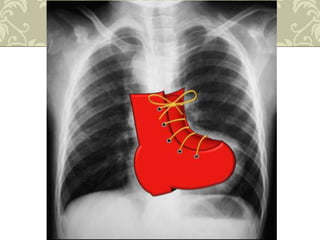

 Hipertrofia do ventrículo direito = coração

em forma de bota.

Radiografia de tórax

 Coração em forma de bota( couer em sabot);

 Circulação pulmonar diminuída;

 Arco aórtico do lado direito(25%);

 Aorta ascendente é proeminente.